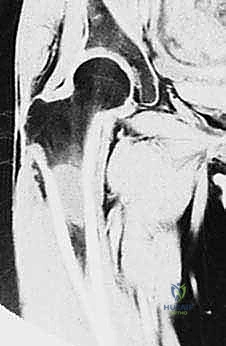

| الرنين المغناطيسي (MRI) | (المعيار الذهبي) يوفر صوراً فائقة الدقة للأنسجة الرخوة، العضلات، الأعصاب، الأوعية الدموية، وامتداد الورم داخل نخاع العظم. | أساسي لتحديد "الهوامش الجراحية الآمنة" ومعرفة ما إذا كان الورم قد مس الأعصاب أو الأوعية. |

- تحديد الهوامش الجراحية (Surgical Margins): بناءً على صور الرنين المغناطيسي، يحدد الدكتور هطيف بالضبط أين سيقطع العظم. الهدف هو إزالة الورم مع غلاف من الأنسجة السليمة المحيطة به (هامش واسع) لضمان عدم ترك أي خلية مريضة.

- الحفاظ على المحفظة (Capsule Preservation): في معظم الحالات الجراحية القياسية التي يجريها الأستاذ الدكتور محمد هطيف، يمكن الحفاظ على محفظة مفصل الورك السليمة، ويتم إجراء استئصال لرأس وعنق الفخذ من داخل المفصل (Intra-articular Resection). ومع ذلك، إذا أظهرت الفحوصات الدقيقة قبل الجراحة (مثل الرنين المغناطيسي) أو الملاحظات أثناء الجراحة وجود أي اشتباه لانتشار الورم إلى المحفظة أو الحُق، فإن الأستاذ الدكتور هطيف يكون مستعداً تماماً لإجراء استئصال خارج المفصل (Extra-articular Resection)، وهو إجراء أكثر تعقيداً يتضمن إزالة المفصل بأكمله ككتلة واحدة لضمان عدم ترك أي خلايا سرطانية، مما يغير بشكل كبير من استراتيجية إعادة البناء.